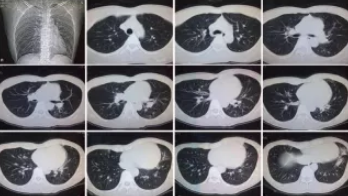

CT檢查原理是X光分層穿過人體,這就像把面包切成薄片,每一片都可以攤開看。當遇到外傷懷疑傷到骨頭,可以選擇CT觀察隱匿損傷或軟組織損傷。

CT適用于頭部、胸部、腹部、盆腔、脊柱、四肢、骨骼等處,由于它的特殊診斷價值,已經廣泛應用于臨床,特別是在腫瘤的診斷上更是具有很高的應用價值。但由于CT設備較為昂貴,檢查費用也會偏高,對于某些部位的檢查和診斷價值,尤其是定性診斷,還有一定限度,所以在臨床上并沒有將CT檢查視為常規(guī)診斷手段。此外,CT診斷輻射量大于DR,所以懷孕或備孕期女性不宜進行CT檢查。